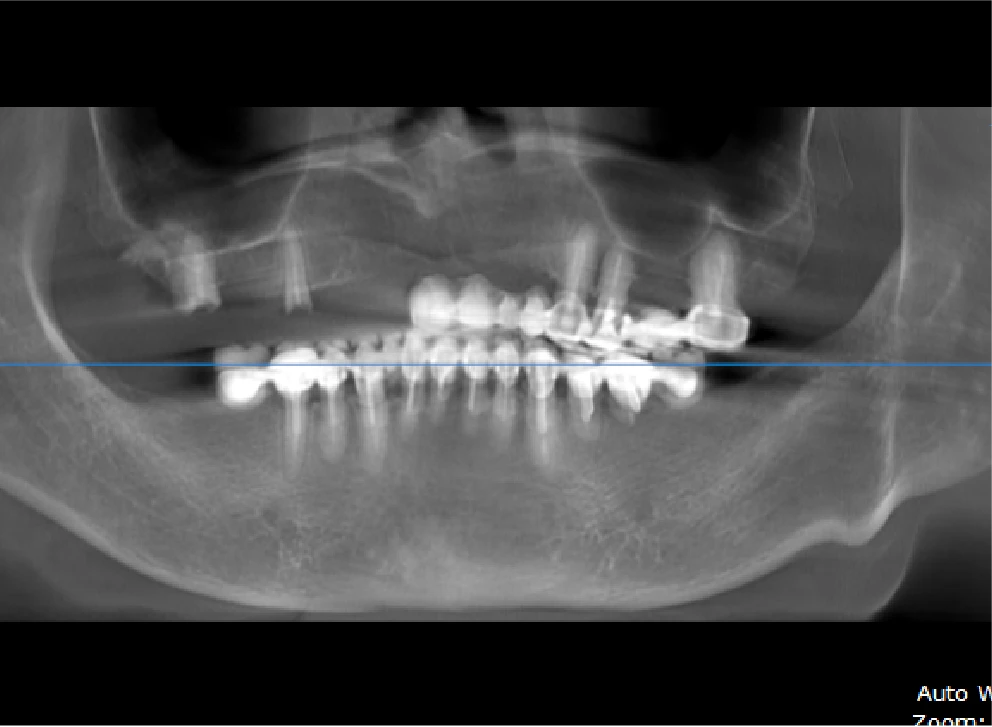

• Tình trạng răng trước đây:Mất răng toàn hàm trên và hàm dưới nhiều răng lung lay.

• Bác sĩ chỉ định:Cấy ghép 2 hàm Implant All On 6.

• Implant sử dụng:Implant Mis C1 Đức.

• Cấy ghép 2 hàm Implant All On 6

• Phục hình răng sứ trên Implant